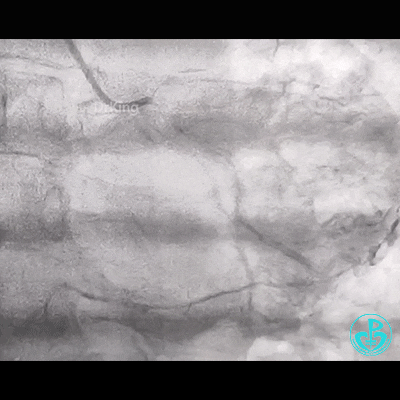

冠脉造影

右锁骨下动脉迂曲打圈,影像如下: